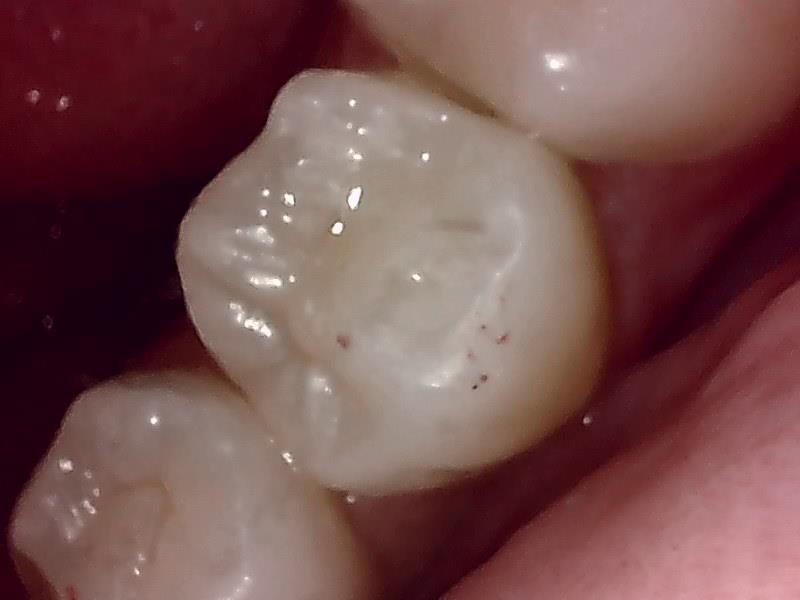

保険レジン充填の症例

Before

After

| 主訴 | 保険レジン充填の症例 |

|---|---|

| 診断名 | 虫歯治療 |

| 年齢・性別 | 10代 女性 |

| 治療方法 | コンポジットレジン充填 |

| 費用 | 保険診療 |

| デメリット・注意点 | 金属(メタル)やセラミックと比較すると強度が低いため、硬いものを噛んだり、強い衝撃が加わると再破折するリスクがあります。 |